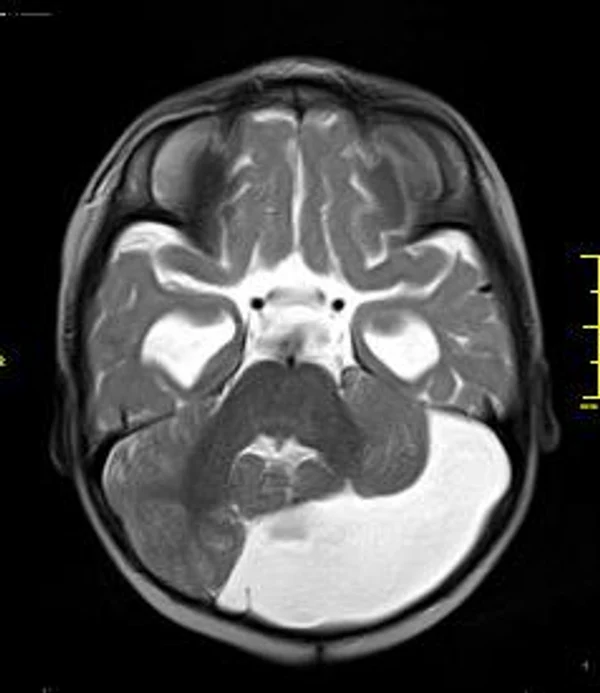

кисты, аномалии Денди-Уокера и др.Операции при внутричерепных кистах. В основном встречаются арахноидальные кисты различных локализаций и кисты сосудистых сплетений боковых желудочков. Пациентам с врождёнными кистами операции проводятся в следующих ситуациях: увеличении объема кисты в динамике, наличии клинических проявлений, компрессии и дислокации мозговых структур, наличии окклюзии ликворных путей. Нами используются 2 способа хирургического лечения кист: эндоскопическая перфорация стенок кист и открытая резекция кист. Открытая резекция кист проводится при ретроцеребеллярных арахноидальных кистах (рис. 2), при арахноидальных кистах межполушарной щели при отсутствии непосредственного контакта их стенок со стенками расширенных желудочков головного мозга и повторного увеличения кист средней черепной ямки после эндоскопической кисто-цистерностомии. Техника операции заключается в проведение краниотомии и максимальном иссечении стенок кист с созданием широкого сообщения кист с субарахноидальным пространством. Эндоскопические операции проводятся при арахноидальных кистах межножковой и пинеальной цистерн, арахноидальных кистах межполушарной щели при тесном контакте их стенок со стенками расширенной желудочковой системы (рис. 3), первично при арахноидальных кистах средней черепной ямки, а также при кистах сосудистых сплетений боковых желудочков. При арахноидальных кистах межножковой цистерны эндоскопически проводится перфорация стенок кисты, сообщая ее с просветом III желудочка и межножковой цистерной – эндоскопическая вентрикуло-кисто-цистерностомия (рис. 4). При арахноидальных кистах пинеальной цистерны проводится перфорация кисты в передне-верхних её отделах с созданием сообщения полости кисты с просветом III желудочка – эндоскопическая кисто-вентрикулостомия. С целью предотвращения облитерации сформированного отверстия иногда в полость кисты под контролем эндоскопа вводится стент перфорированный на протяжении (рис. 5, 6). Эндоскопическая кисто-цистерностомия выполняется при арахноидальных кистах средней черепной ямки. При этом создается широкое сообщение кисты с базальными цистернами. При кистах сосудистых сплетений боковых желудочков проводится их вскрытие в просвет боковых желудочков – эндоскопическая кисто-вентрикулостомия. При множественных кистах проводится их хирургическое сообщение между собой – интеркистосмия